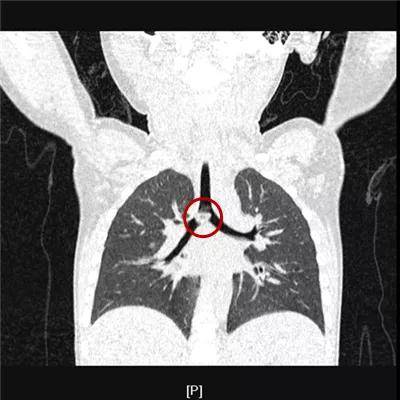

1岁·瓜子

5小时余前食用瓜子后有可疑呛瓜子,后出现咳嗽伴气喘。位于气管分叉处,您还能看出瓜子君的本来面目吗?